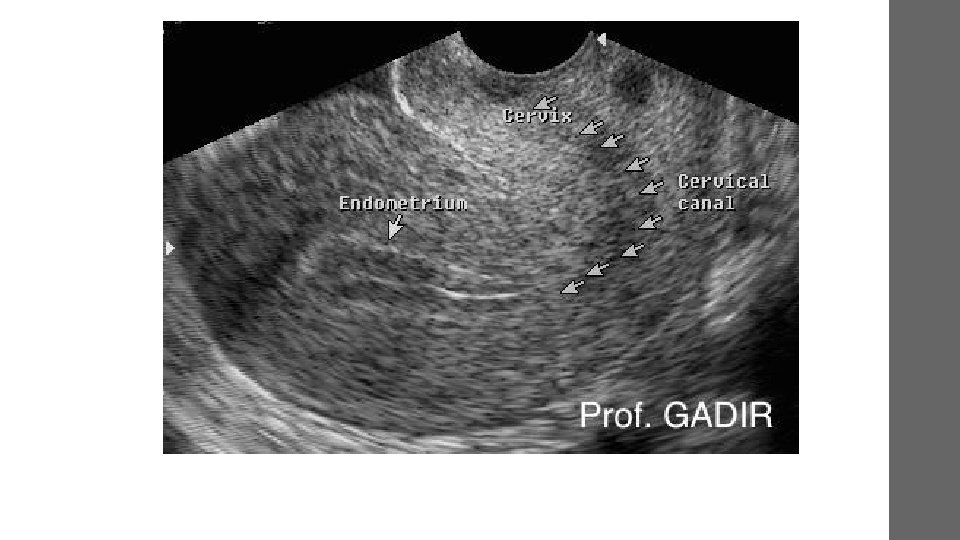

• heart and blood vessels • Liver • Gallbladder • unborn child (fetus) in pregnant patients • Eyes • Thyroid and parathyroid glands • Scrotum • brain in infants • hips in infants • Spleen • Pancreas • Kidneys • Bladder • Uterus and ovaries,